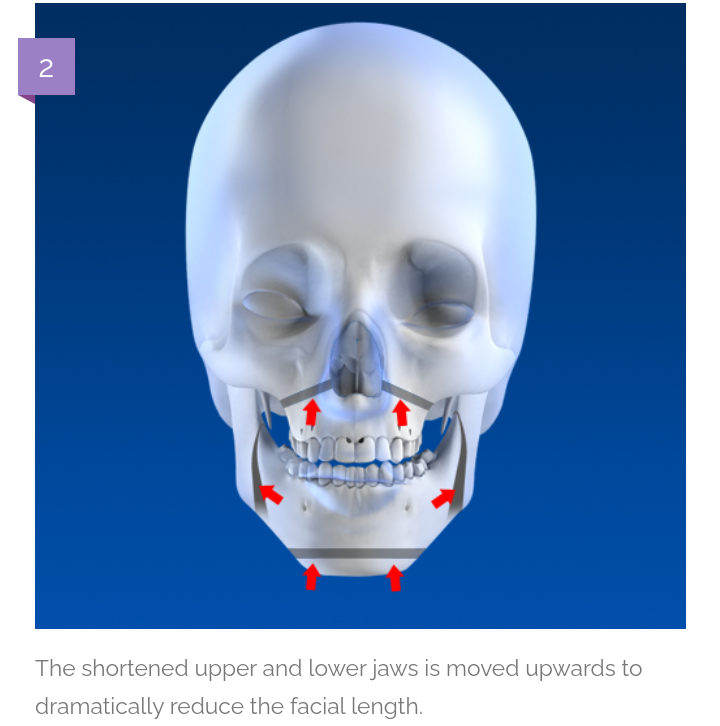

02 exacly cause of long midface

How the surgery look?

Shorter nose and Reversed most of the downward growth

02 exacly cause of long midface

How the surgery look?

Shorter nose and Reversed most of the downward growth